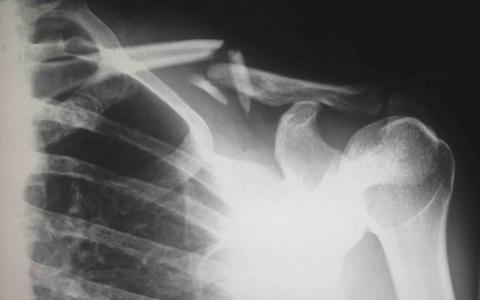

Serious back injuries can result from car accidents, activity at work, or from a slip and fall at a place of business such as your local supermarket or post office. The lower back is the most common site of back injuries and back pain. Common back injuries include:

• Strains and Sprains,

• Herniated or Bulging Discs, and

• Fractured Vertebrae

Back injuries are the most common reasons for missed work. Possible long-term effects of an untreated back injury include paralysis of the lower back, chronic pain, prolonged suffering and discomfort, and loss or impairment of movement. Many times, what is initially considered a minor accident can result in damage to the muscle, bone, the spinal cord, or the discs between the vertebrae.

(image courtesy of Harlie Raethel)